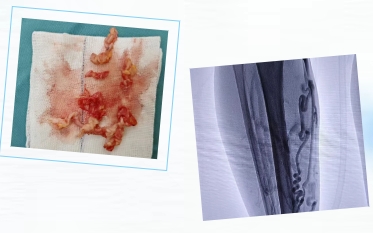

术中,薛崇飞副主任医师通过大隐静脉主干射频消融术将热能导入病变的大隐静脉腔内,使静脉壁受热挛缩、闭合,最终纤维化闭塞。

多措并举,解除静脉分支曲张

对于腿部已经明显曲张、成团的静脉分支,薛崇飞副主任医师通过血管瘤硬化剂注射术,将泡沫化的硬化剂注射入曲张静脉内使其粘连闭合。结合曲张静脉点式剥脱术,在曲张静脉处做数个3mm的微小切口,将静脉分段钩出切除。